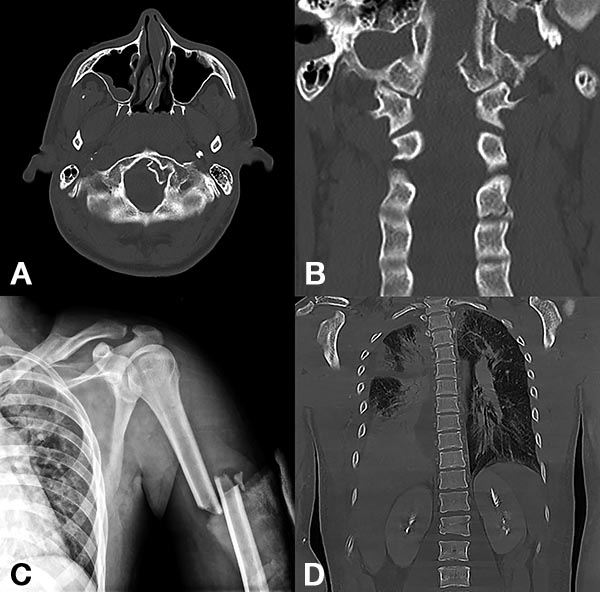

Figura 1:

Caso 24. Hombre 21 años con politraumatismo por accidente vial. A y B: Fractura del cóndilo occipital izquierdo. C: Fractura expuesta del húmero izquierdo y clavícula. D: Contusión pulmonar más hemotórax derecho.